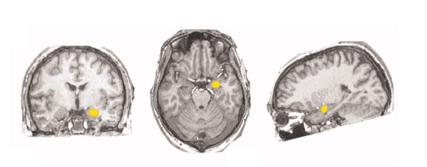

大脑中不同位置的杏仁核|参考文献[8]

原来,尼古丁成瘾有一个核心特征——吸烟线索反应(smoking cue reaction),即对与吸烟相关的提示表现出显著的生理和主观反应。在这个过程中,吸烟成瘾者大脑中的杏仁核会消耗更多氧气和营养物质,引起循环系统发送更多高氧血液,从而导致激活区域的血氧水平增加。吸烟线索反应可能是复吸发作的重要诱发因素,也可能从根本上影响着戒烟者的控制能力。